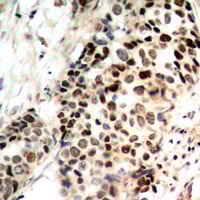

IHC (Immunohiostchemistry)

(Immunohistochemical analysis of Histone Deacetylase 3 (pS424) staining in human breast cancer formalin fixed paraffin embedded tissue section. The section was pre-treated using heat mediated antigen retrieval with sodium citrate buffer (pH 6.0). The section was then incubated with the antibody at room temperature and detected using an HRP conjugated compact polymer system. DAB was used as the chromogen. The section was then counterstained with haematoxylin and mounted with DPX.)